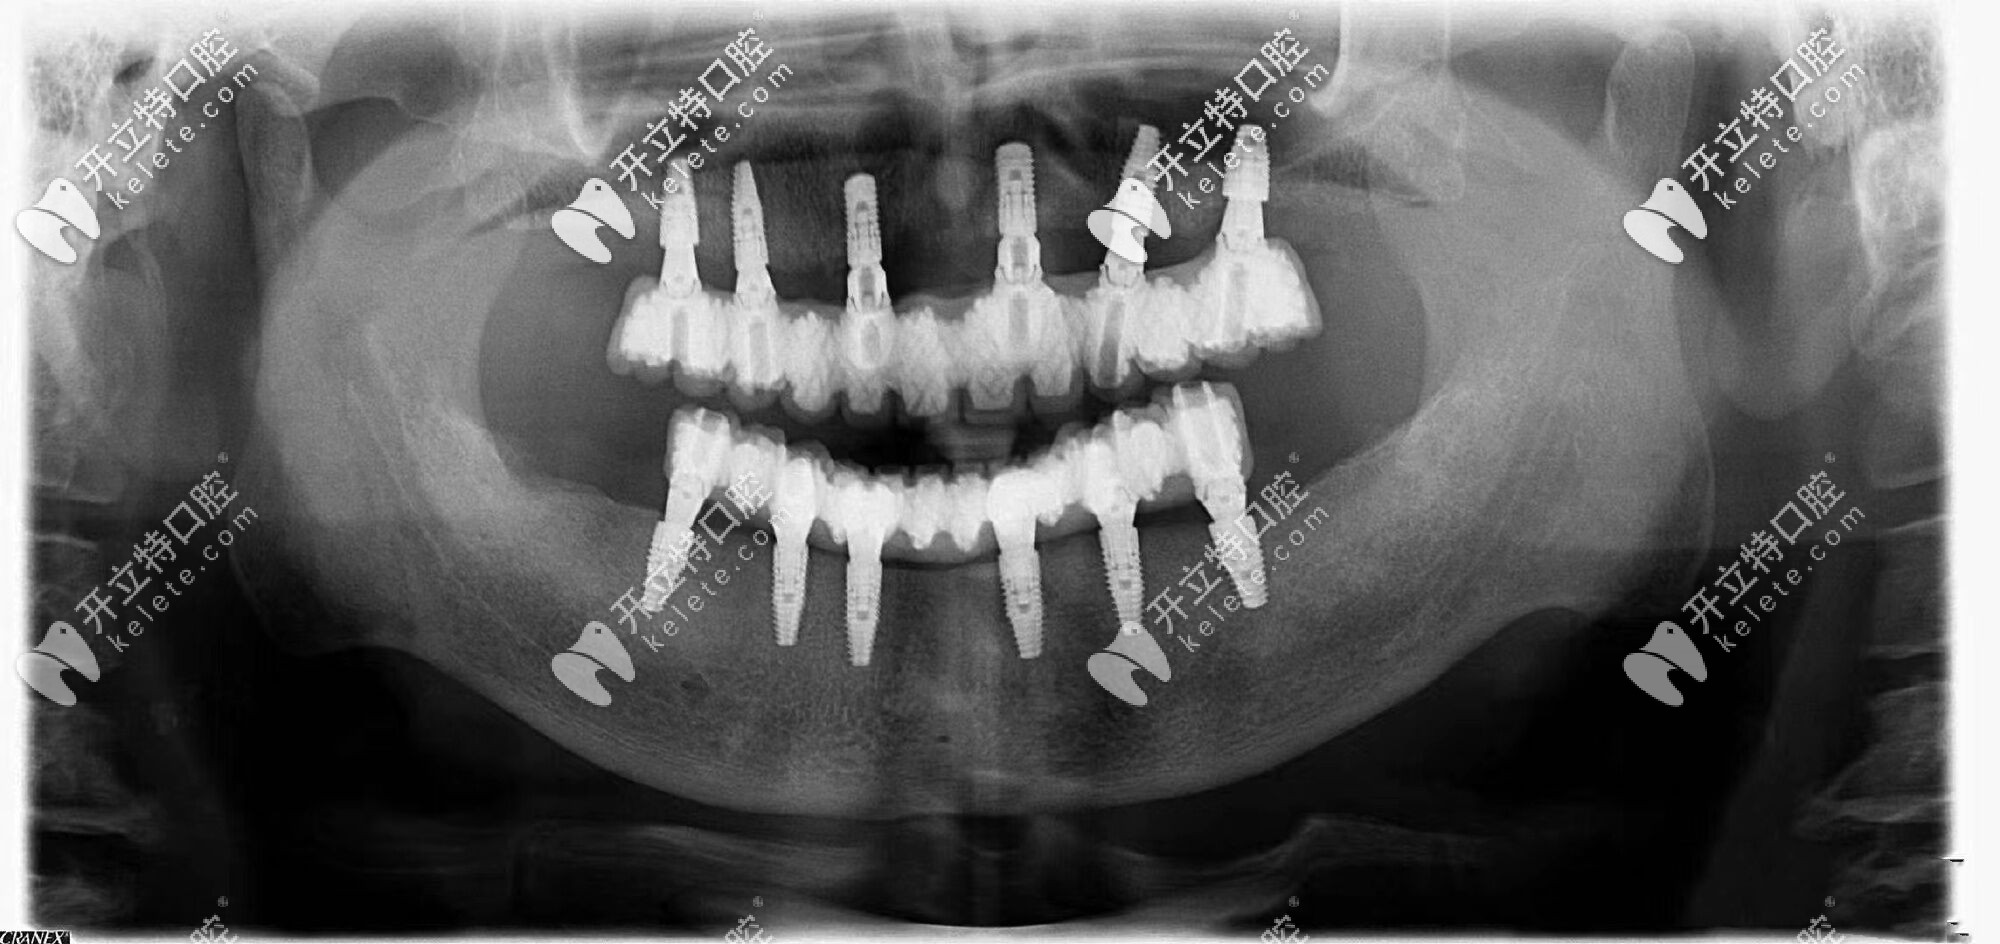

由于常年戴活動(dòng)假牙,導(dǎo)致自身牙槽骨的條件較差,醫(yī)生給張叔設(shè)計(jì)了全口即刻種植牙的方案,沒(méi)想到3個(gè)小時(shí)左右的時(shí)間就完成了種植牙,并且真的是當(dāng)天種牙,當(dāng)天吃飯??!

沈陽(yáng)歡樂(lè)仁愛(ài)口腔的即刻修復(fù),讓張叔沒(méi)有無(wú)牙的空窗期,不僅恢復(fù)了咀嚼進(jìn)食功能,更保證了發(fā)音和美觀,大幅度提升了晚年的幸福指數(shù)。